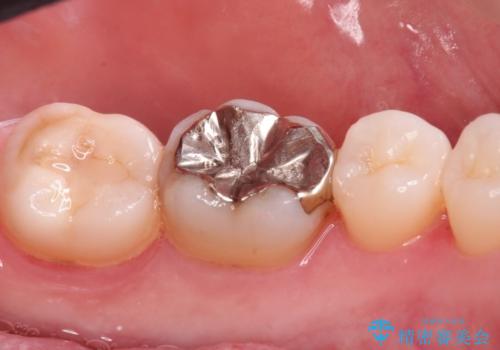

- 銀の詰め物が目立つので白くしたいとのことで来院。

拡大鏡下で銀の詰め物を除去して虫歯がない事を確認して

白い詰め物(e-maxインレー)にてやりかえを行いました。